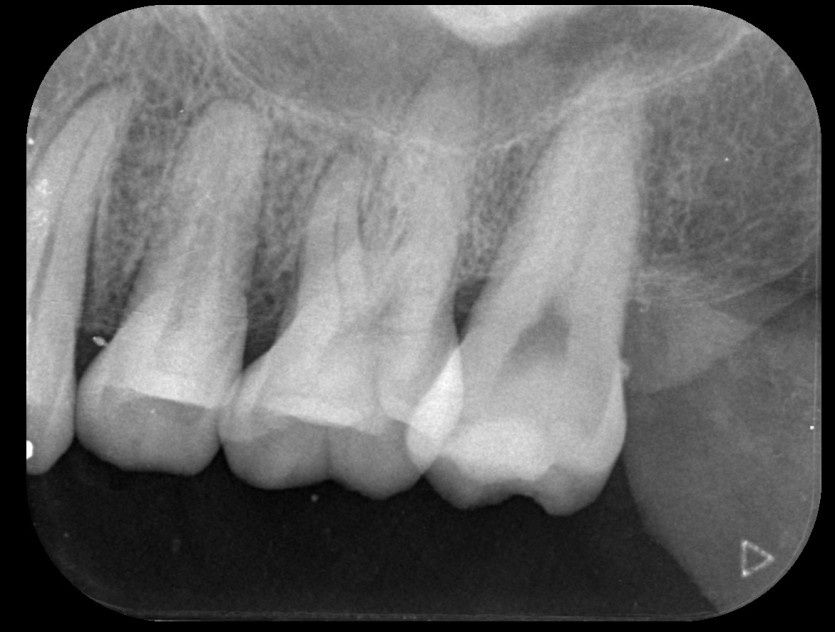

신경치료 사례